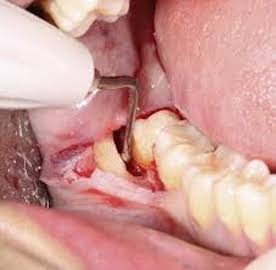

Power regulation: The device should support adjustable power of 3-80W to meet different surgical needs (such as alveolar bone repair and impacted tooth extraction).

Standard working tip: including at least bone incision, ligament resection, maxillary sinus mucosal separation and other types, with a recommended quantity of 8-14 pieces, covering common clinical scenarios.

Compatibility: Supports the selection of different models of work tips to meet personalized surgical needs (such as pediatric dentistry and complex implant surgery).